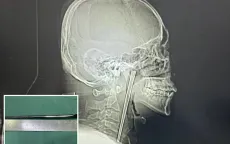

Hy hữu người đàn ông Trung Quốc sống 8 năm với chiếc đũa kim loại mắc trong cổ họng VTV.vn - Một trường hợp y khoa hiếm gặp vừa được ghi nhận tại Trung Quốc.